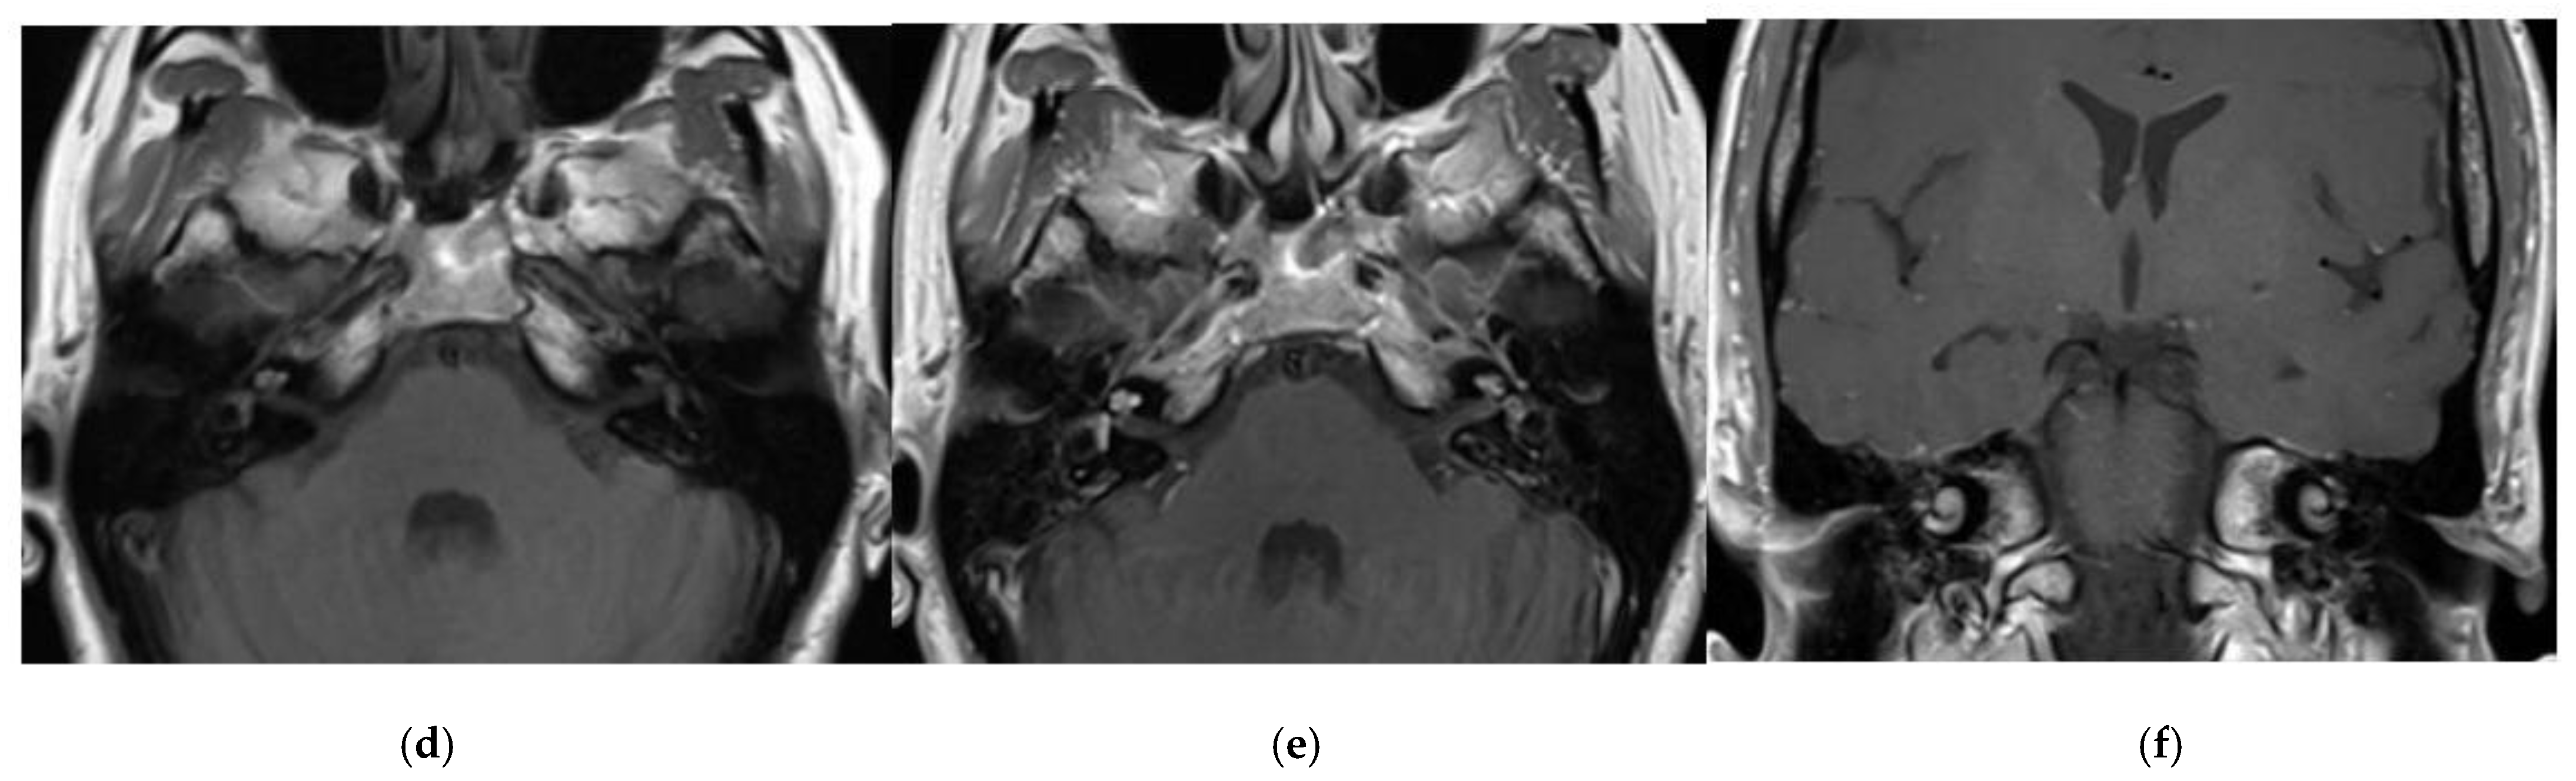

3.1. CASE 1

3.2. CASE 2